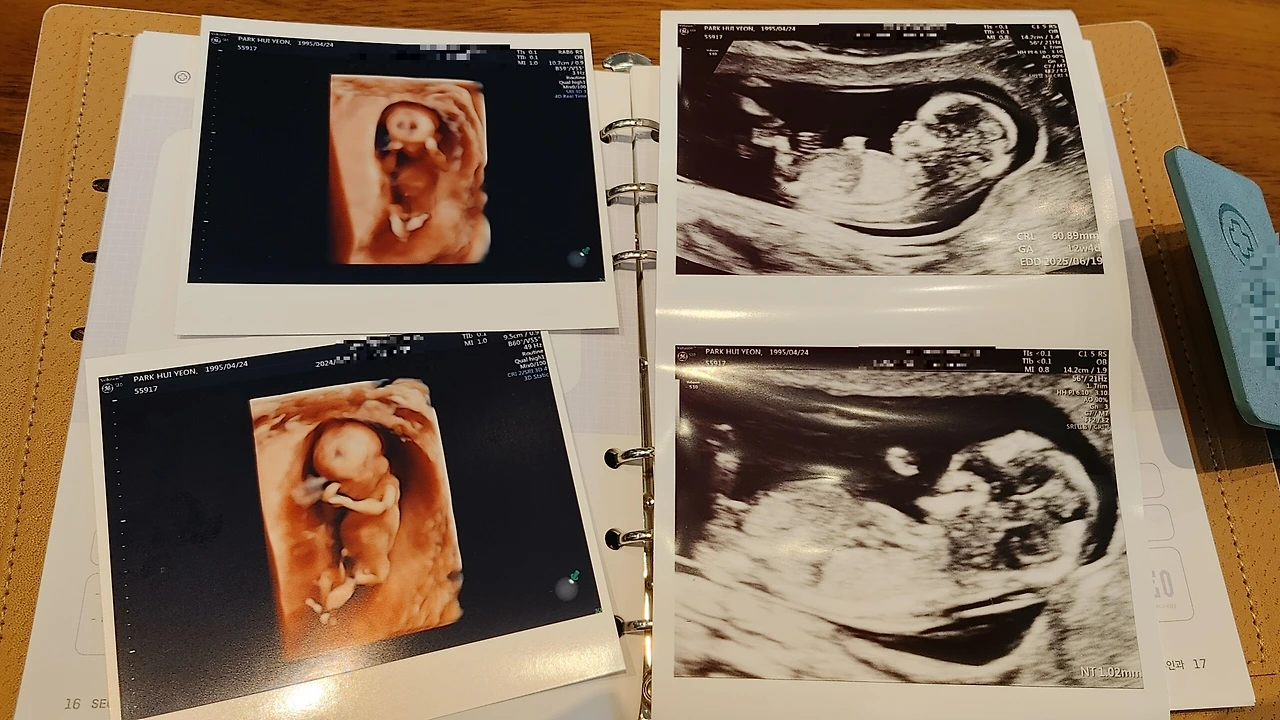

대학원 2학기로 바쁜 나날을 보내던 시월의 어느날, 우리는 기쁜 소식을 접했다.

1트만에 엄마 뱃속에 딱하니 바로 붙어버린 이녀석, 대견하다.

하루하루 아내의 배가 불러오는 것이 신기하고 아기의 150회 두근거리는 심박수가 더욱 신기하다.

오개월 즘 되니 태동이 시작됐는데 이녀석, 우릴 닮아 야행성인지 새벽 세 시만 되면 엄마의 배를 발로 차는 게 아닌가. 물론 아내도 올빼미라 새벽 세시까지 잠을 안 자긴 한다마는, 어쩔 때는 배가 불룩 튀어나올 정도로 몰캉이는 게 보인다.